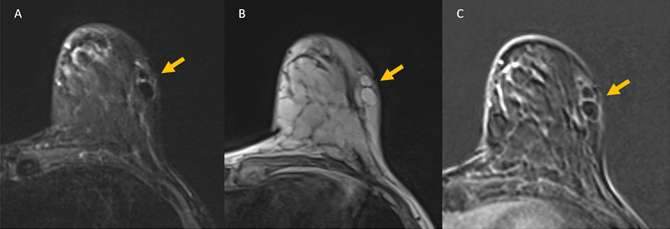

MRI Findings: MRI can be useful when evaluating indeterminate mammographic or ultrasound findings.

Fat necrosis will follow the signal of fat on all MRI sequences. On T1-weighted images, fat necrosis can present as a heterogeneous mass, with areas of intrinisically bright T1 signal centrally. On fat saturation sequences, fat necrosis will lose signal similar to adjacent fatty breast tissue. On STIR sequences, the area of necrotic fat takes on a characteristic “black hole” appearance with greater signal suppression than normal breast fat.6

In the acute phase, avid peripheral or internal enhancement may be seen, corresponding with areas of developing granulation tissue. The degree of enhancement may decrease over time, as fibrosis develops surrounding the area of injury.7 Enhancement kinetics are variable, with persistent enhancement (type I) being the most common, though plateau and washout kinetics may also be seen (type II and type III).